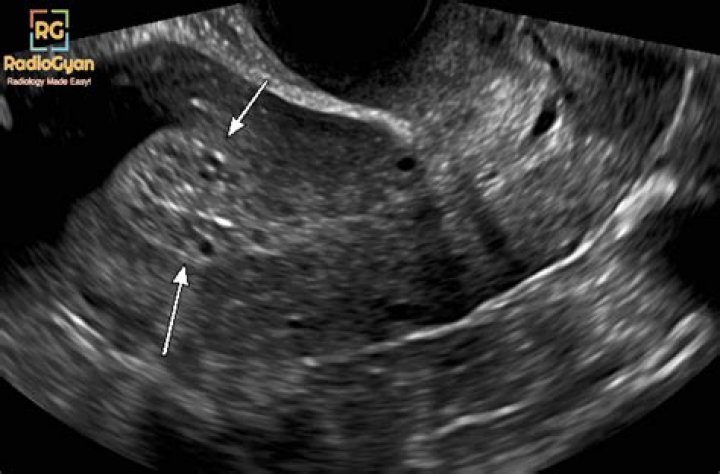

Is endometrium thick before period?

The part of your cycle between when you ovulate and when your period starts is called the secretory phase. During this time, your endometrium is at its thickest. The stripe accumulates fluid around it and, on an ultrasound, will appear to be of equal density and color throughout.